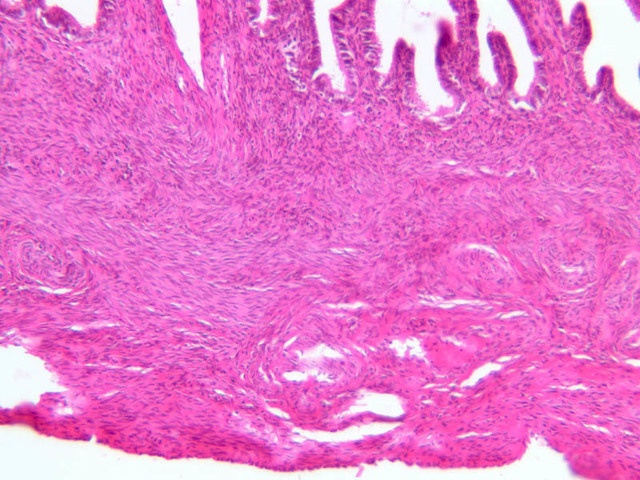

The wall of the uterine tube consists of three layers; a mucosa, a muscularis, and an adventitial/serous coat (B-96 [2.5x, 10x-labeled, 20x, 40x] [2.5x, 10x, 20x, 40x]; B-97, monkey uterus [2.5x, 10x, 20x, 40x]). The mucosa is organized into folds that vary in their degree of complexity with the tube regions. The mucosa is lined by a simple columnar epithelium consisting of two cell types, ciliated and non-ciliated, secretory (B-93 [10x, 20x, 40x-labeled]). The mucosal lamina propria consists of somewhat loose connective tissue and is highly vascular. No muscularis mucosae are present. The muscularis consists of two layers of smooth muscle, the inner being oriented in a circular fashion and the outer longitudinally.

The structure of the uterine tube is under the control of, and responds to, cyclic changes in the levels of steroid hormones. Structural alterations to provide favorable transport for the oocyte commence anew with the beginning of each cycle and peak at mid-cycle just before ovulation. These include increases in height and number of the ciliated cells as well as active secretion in the secretory cell. For the remainder of the cycle thereafter, dedifferentiation occurs. The cyclic changes occur to a greater extent in the upper ampulla and infundibulum. The margin of the infundibulum is drawn out into numerous finger-like processes called fimbrae. Microscopic examination of these will reveal that within the lamina propria are numerous large blood vessels, especially veins, as well as bundles of smooth muscle forming an intervening network. At the time of ovulation, the vessels become enlarged with blood, causing turgidity, which when combined with smooth muscle contraction brings the infundibular opening into close apposition with the ovarian surface.